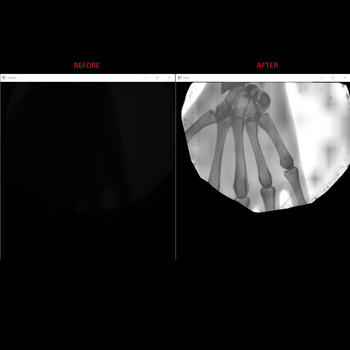

2 yıldır PHP,C# dillerini kullanarak bot yazmaktayım. Ayrıca görüntü işleme projelerinde de çalışmaktayım. Ebay, Amazon, Gumtree, Yelp, Zillow, Yellowpages, Manheim, Instagram, Twitter, Aircanada, Kellyservices, Gittigidiyor, BransonTractors, çeşitli e-ticaret siteleri, çeşitli iş ilanı siteleri gibi farklı sitelere bağlanarak otomatik olarak veri çeken uygulamalar yazmaktayım. * Fiyat karşılaştırma uygulamalarının backend kısmında çalıştım. Örneğin: https://lmctplus.com https://teslacarsearch.com/ https://www.savime.co/en/Riyadh/Saudi/privacypolicy * Amerika'da taşınabilir X-Ray cihazı yapan bir şirket için görüntü iyileştirme kütüphanesi yazdım: http://www.microcimaging.com/ * Rubik küp tespit eden program yazdım. (C++ ile). Kodları için: https://gist.github.com/fkose1993/4d0455247008813b712dca6f897d8d9a * Ayrıca SURF algoritmasını kullanarak özellik noktaları yardımı ile gerçek zamanlı nesne algılayan MATLAB kodu yazdım. (Bitirme projesi)